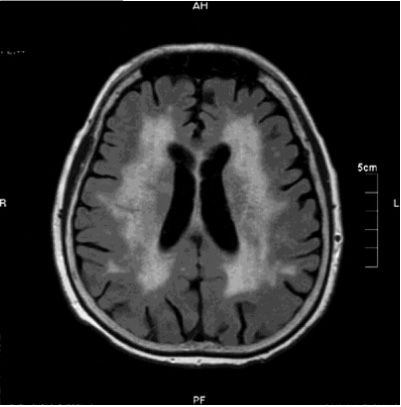

• 画像診断で「多発大梗塞・重要な領域の単発梗塞・多発性の基底核ないし白質の小梗塞あるいは広範な脳室周囲白質の病変」などを認める

血管性認知症の画像

MRIによる画像

血管性認知症のMRI画像